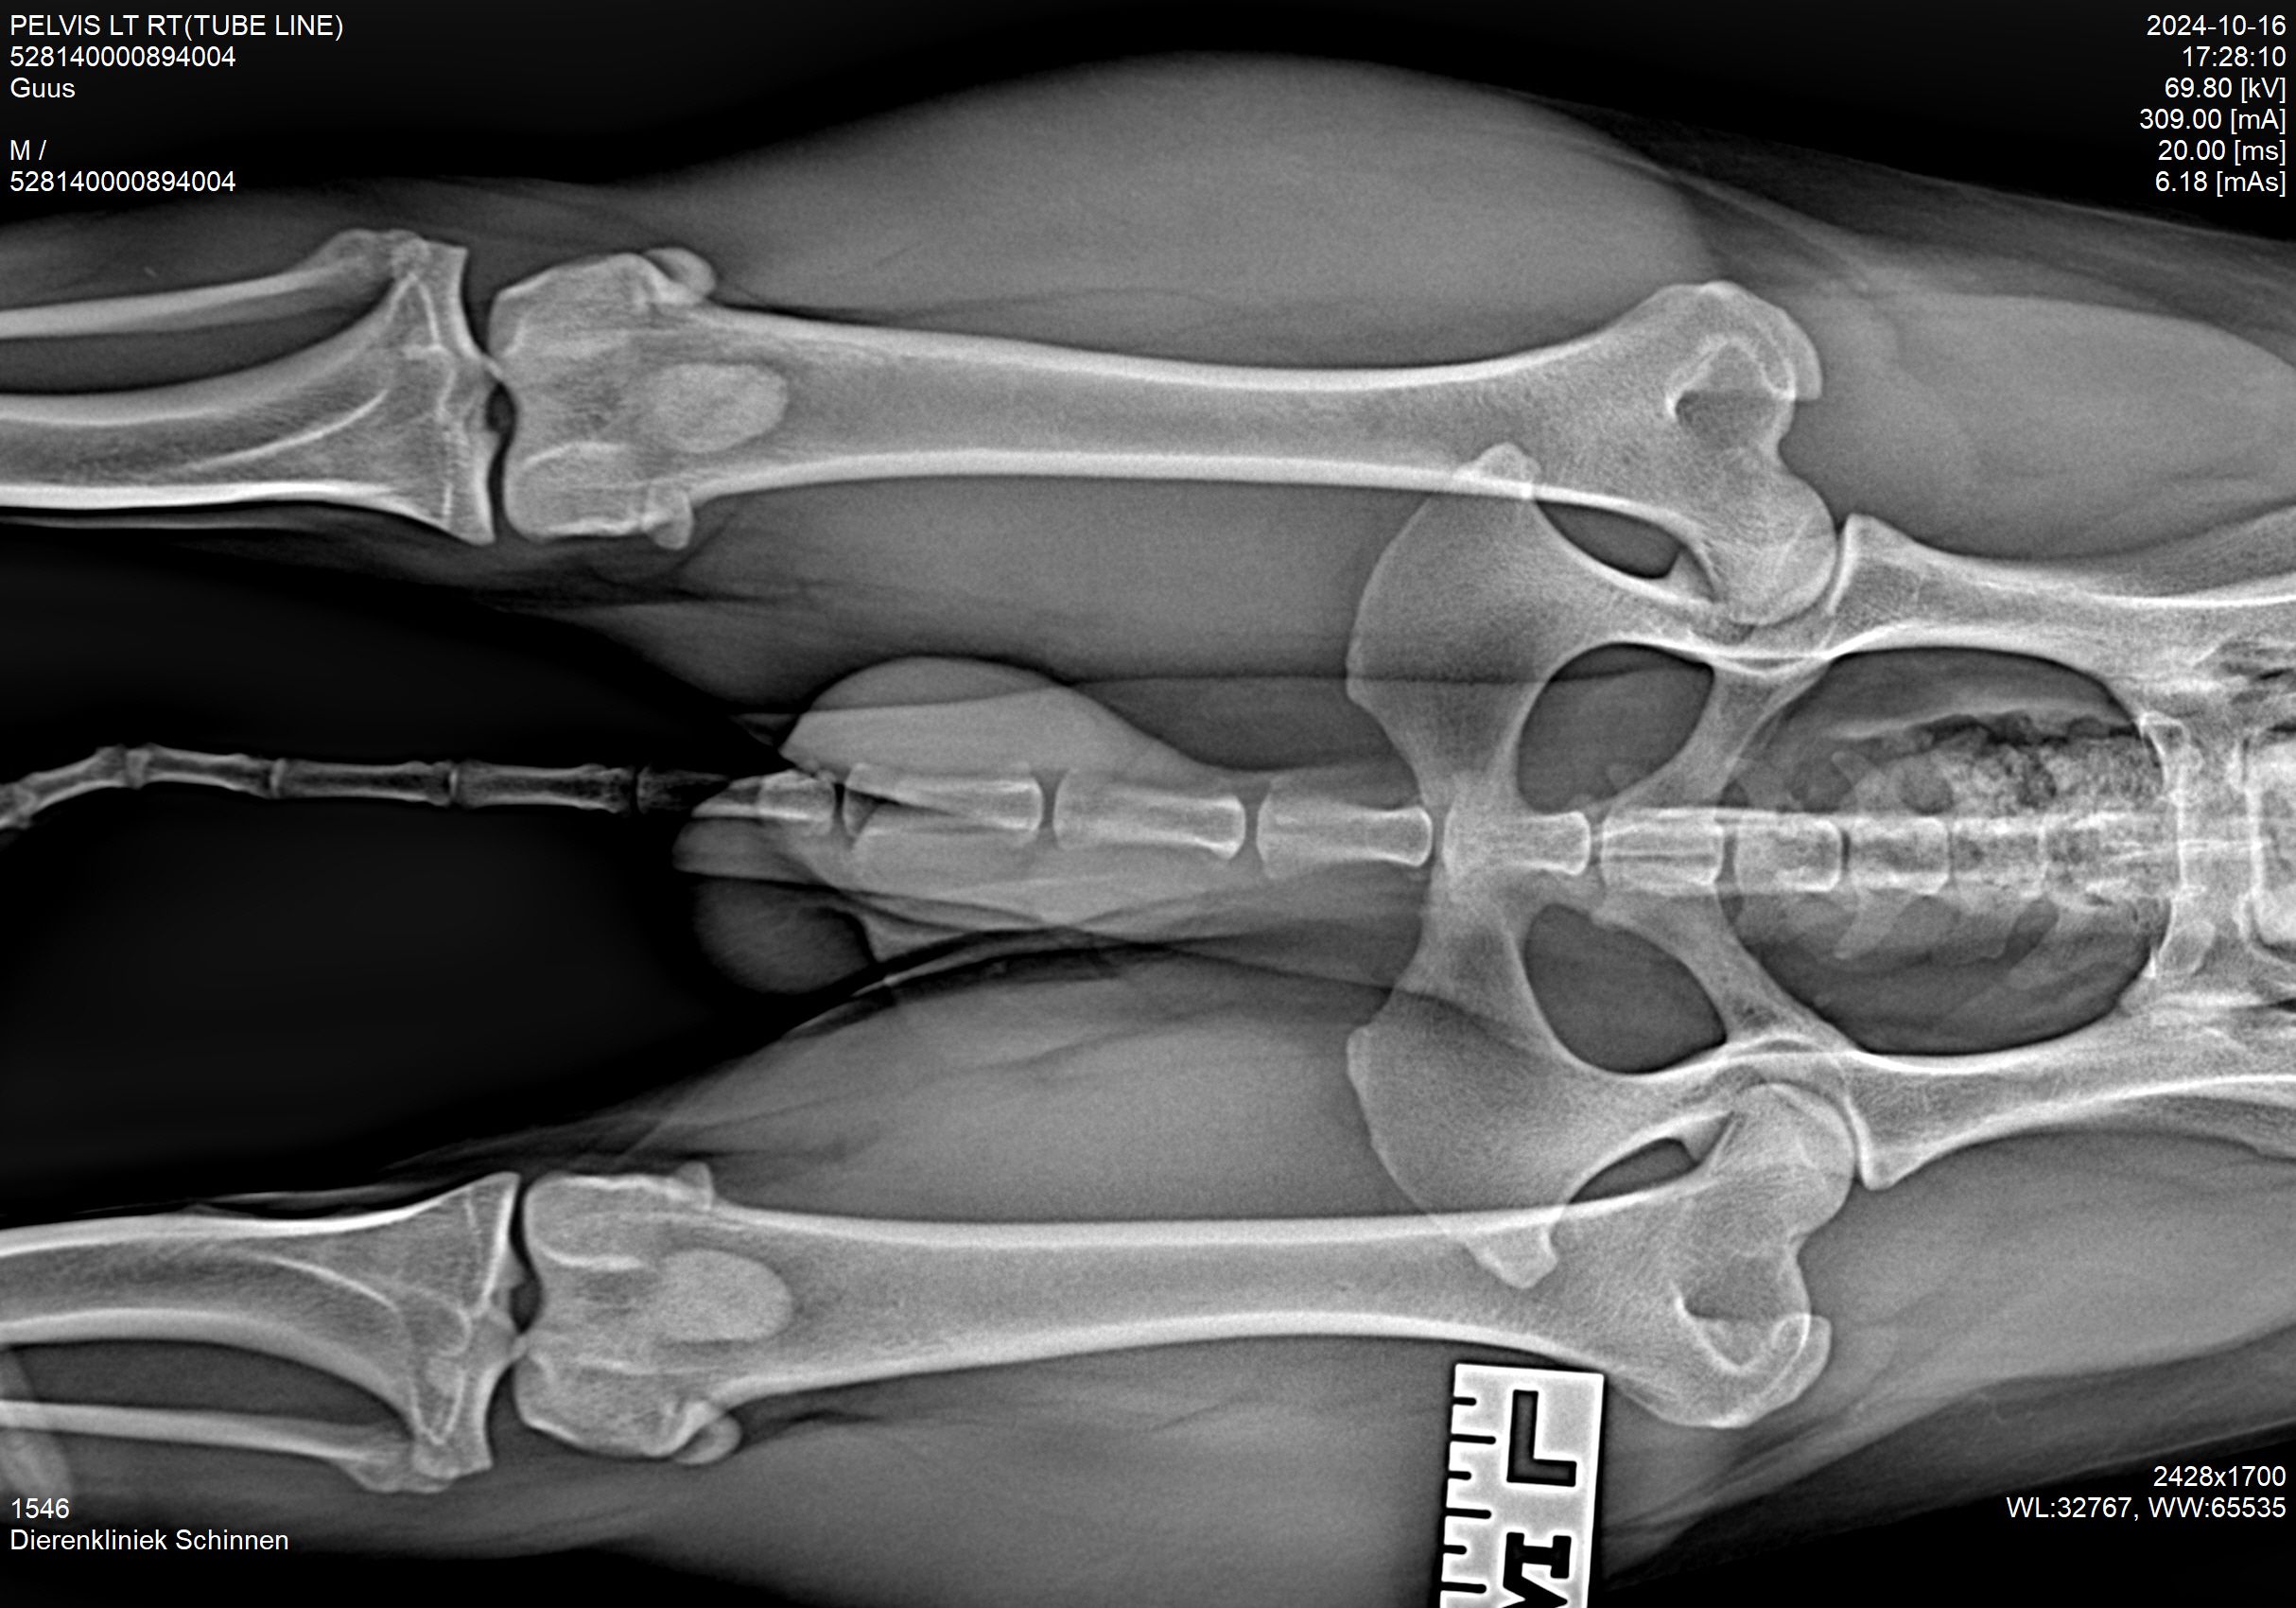

Hieronder foto's van Guus genomen met onze nieuwe DRgem rontgen. Beoordeeld met de hoogste score door de Raad van Beheer op Kynologisch gebied

Meestal passen wij een sedatie toe bij het maken van de officiële HD-foto’s. Dit is nodig om een kwalitatief goede foto te maken, welke aan de hoge eisen van de beoordelingscommissie moet voldoen. Uw hond moet op zijn of haar rug liggen, waarbij het bekken en de achterpoten symmetrisch worden gestrekt en de knieschijven moeten op juiste manier worden ingedraaid.